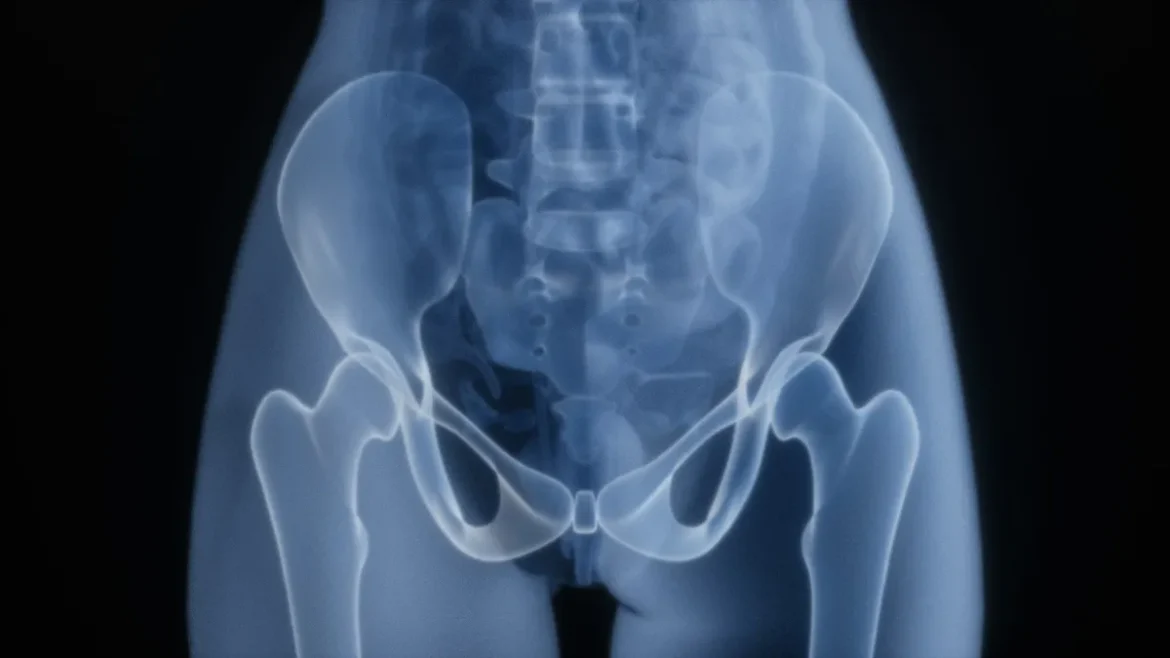

Sokan tévesen hiszik, hogy a csípőfájdalom kizárólag az idősebb korosztály sajátja, pedig ez nem igaz. Ez a probléma bárkinél jelentkezhet, függetlenül az életkortól, és komoly figyelmet igényel. A csípőfájdalom hirtelen felléphet, és megnehezítheti a mindennapi mozgást, így az orvosi segítség keresése elengedhetetlen.

Fontos tudni, hogy a csípőfájdalom kezeléséhez gyakran nem szükséges műtéti beavatkozás. Az első lépés a pontos diagnózis felállítása, amelyhez orvosi vizsgálatok, röntgen vagy MRI segítségével juthatunk el a valódi okok feltárásához. A fájdalom enyhítésére számos alternatíva létezik: